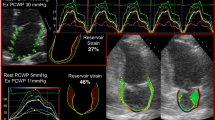

In the healthy heart, both early diastolic suction (increasing mitral valve flow) and myocardial relaxation are augmented during exercise; thus, E/e′ ratio is preserved. In a group of 74 consecutive patients with EF ≥ 50% referred for haemodynamic investigations for exertional dyspnoea, elevated PCWP (≥ 25 mmHg) was evident during exercise in around a third of patients [26]. Addition of exercise E/e′ to resting E/e′ improved sensitivity for identifying patients with HFpEF to 90%, albeit the cost of reduced specificity (75%).

Current guidelines recommend exercise echocardiography in patients with indeterminate resting measurements (i.e. grey-zone E/e′) and in patients with diagnostic uncertainty [5]. Recently, LA strain measured using speckle-tracking echocardiography at rest has shown comparable sensitivity and specificity (86% and 79%, respectively) for identifying elevated exercise PCWP [28]. The utility of exercise LA strain is yet to be determined.